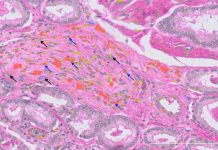

Cercetătorii australieni au dezvoltat cel mai detaliat atlas celular al cancerului de prostată până în prezent, identificând schimbări moleculare timpurii care nu sunt detectabile prin metodele diagnostice actuale bazate pe patologie. Studiul, publicat astăzi în revista Cancer Research, a dezvăluit de asemenea existența unui tip de celulă necunoscut până acum, care ar putea juca un rol în dezvoltarea cancerului de prostată.

Rezultatele pacienților cu cancer de prostată sunt extrem de variabile, variind de la cancere indolente care nu reprezintă o amenințare imediată la boli metastatice care avansează rapid. Metodele prognostice actuale se bazează pe analiza unui patolog a probelor de biopsie, concentrându-se pe diferențele vizuale și structurale între celulele canceroase și cele sănătoase. Totuși, studiul a arătat că multe celule care arată sănătoase conțin deja alterări genomice ce stimulează cancerul.

Cercetătorii au analizat probe de biopsie de la 24 de pacienți diagnosticați recent cu cancer de prostată în stadiu incipient. Toate probele au fost obținute de la Biobanca de Cancer de Prostată Garvan St Vincent, care păstrează material de la peste 16.000 de pacienți. Secvențierea ARN-ului la nivelul unei singure celule și transcriptomica spațială au fost utilizate pentru a examina atât celulele canceroase de prostată, cât și mediul înconjurător, creând o imagine completă a compoziției lor moleculare și distribuției spațiale.

Au fost identificate un total de 11 tipuri majore de celule, 50 de subtipuri minore și numeroase stări celulare, unele dintre ele unice pentru fiecare individ și altele comune între pacienți. Aceasta a dus la identificarea unei noi populații de celule pe care cercetătorii le-au numit fibroblați asociati cancerului perineural, localizați în apropierea nervilor. Deoarece tumorile de prostată care cresc în și în jurul nervilor sunt asociate cu rezultate mai slabe, această descoperire ar putea oferi un punct de plecare pentru a înțelege mai bine rolul lor în metastaza cancerului de prostată.